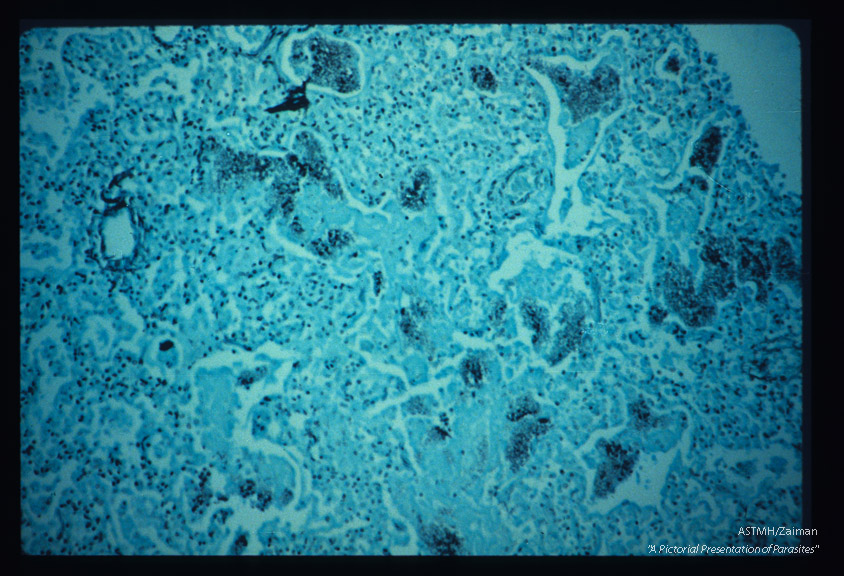

Pneumonia. High power view of infected lung stained with silver methenamine. Parasitic borders are often sharply outlined in black. Fewer nuclei are seen.

Pneumocystis carinii

Description: Pneumonia. High power view of infected lung stained with silver methenamine. Parasitic borders are often sharply outlined in black. Fewer nuclei are seen.